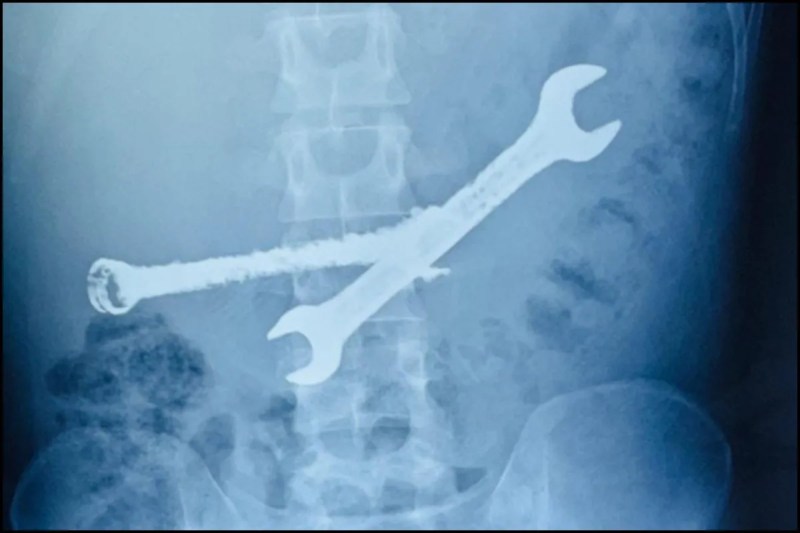

वरिष्ठ गैस्ट्रो सर्जन ने बताया कि भीलवाड़ा का रहने वाला यह युवक असहनीय पेट दर्द की शिकायत लेकर आया था। जब एंडोस्कोपी की गई, तो मॉनिटर पर दिख रही तस्वीरों ने सबको चौंका दिया। पेट के अंदर लोहे के औजार और प्लास्टिक के ब्रश आमाशय की दीवार को छलनी करने ही वाले थे।

डॉक्टर्स के मुताबिक, वस्तुएं इतनी नुकीली और सख्त थीं कि उन्हें एंडोस्कोपी (मुंह के रास्ते) से निकालना जानलेवा हो सकता था। ऐसे में टीम ने तुरंत ओपन सर्जरी का फैसला लिया। घंटों चली मशक्कत के बाद एक-एक कर सात ब्रश और दो भारी लोहे के पाने बाहर निकाले गए।